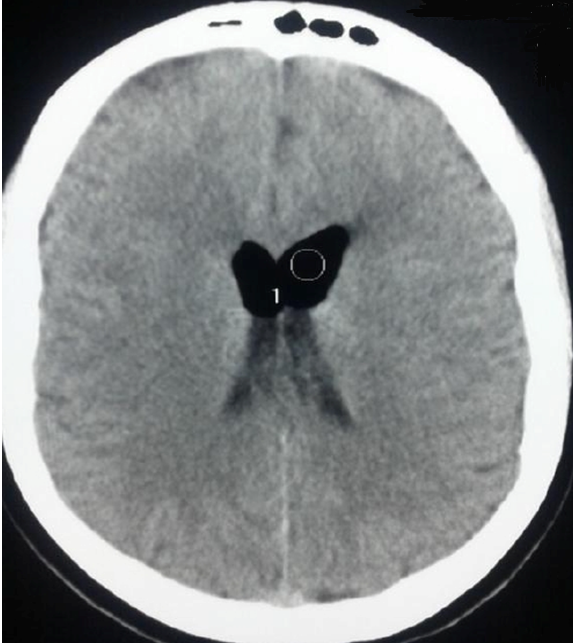

Pneumocéphalie compliquant un Blood patch réalisé pour des céphalées post césarienne

Patiente âgée de 24 ans, consulte aux urgences obstétricales pour des céphalées et des vomissements apparus 48 heures après une césarienne urgente faitesous rachi anesthésie. Ces céphalées étaient intenses, positionnelles, et rebelles au traitement médical pris pendant sept jours (réhydratation, repos, caféine, paracétamol). L'examen clinique n'a pas montré de déficit sensitivomoteur ou de troubles neurosensoriels, la nuque était souple, la température était de 37,2. L'examen cardiorespiratoire était sans particularités. Devant ces céphalées persistantes et invalidantes, le diagnostic d'une brèche dure mérienne a été posé et on a décidé de faire un Blood Patch. Le niveau choisi était L4-L5, en dessous de la ponction précédente avec repérage grâce à une seringue remplie d'air et l'injection de 15 ml de sang autologue prélevé au niveau du pli du coude, ce volume a été déterminé à partir d'une sensation d'une tension au niveau lombaire rapportée par la patiente. Lors de la procédure il y a eu une effraction de la dure mère avec issue du liquide céphalorachidien. Au troisième jour et devant la persistance et surtout l'aggravation des céphalées, une TDM cérébrale a été demandée et a objectivé lapneumocéphalie. L'évolution a été marquée par le tarissement spontané et complet des douleurs après 24heures d'hospitalisation en réanimationaprès laquelle la patiente est sortie à domicile. Cette observation souligne l'importance de réaliser un scanner cérébral devant une non résolution par un Blood patch des céphalées post brèche dure mérienne.